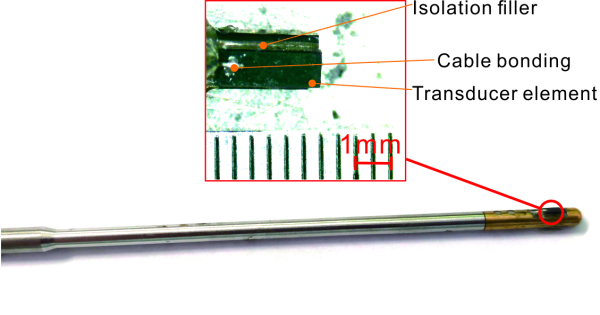

圖1.自制多頻超聲內窺鏡樣品